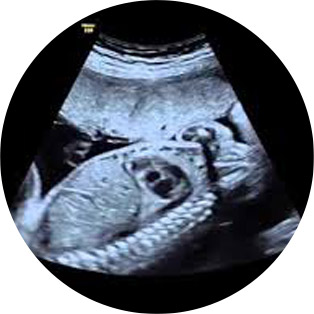

Το υπερηχογράφημα Β’ επίπεδου είναι ο λεπτομερής υπερηχογραφικός έλεγχος του εμβρύου μεταξύ 18-22 εβδομάδων κύησης, που έχει ως σκοπό τη συλλογή με ακρίβεια διαγνωστικών πληροφοριών που θα βελτιώσουν την προγεννητική φροντίδα και θα δώσουν πληροφορίες για τον τοκετό, με τελικό σκοπό την καλύτερη έκβαση της κύησης για τη μητέρα και το έμβρυο.

Πιο συγκεκριμένα, καθορίζεται η ηλικία της κύησης, πραγματοποιούνται μετρήσεις του εμβρύου (βιομετρία) για τον έλεγχο της ανάπτυξής του και ανακαλύπτονται συγγενείς ανωμαλίες του εμβρύου. Η αξιοπιστία της εξέτασης είναι 55% για μείζονες ανατομικές ανωμαλίες του εμβρύου (αυτές που απαιτούν μετά τη γέννηση χειρουργική αποκατάσταση ή οδηγούν σε κάποιου βαθμού αναπηρία).

Στο ιατρείο του Μαιευτήρος – Γυναικολόγου Αλέξανδρου Μάινα, στην Κομοτηνή, το υπερηχογράφημα Β’ επίπεδου πραγματοποιείται με τον υπερσύγχρονο υπερηχοτομογράφο Voluson S 10 GE Healthcare BT16 (1ος εγκατεστημένος στην Β. Ελλάδα).